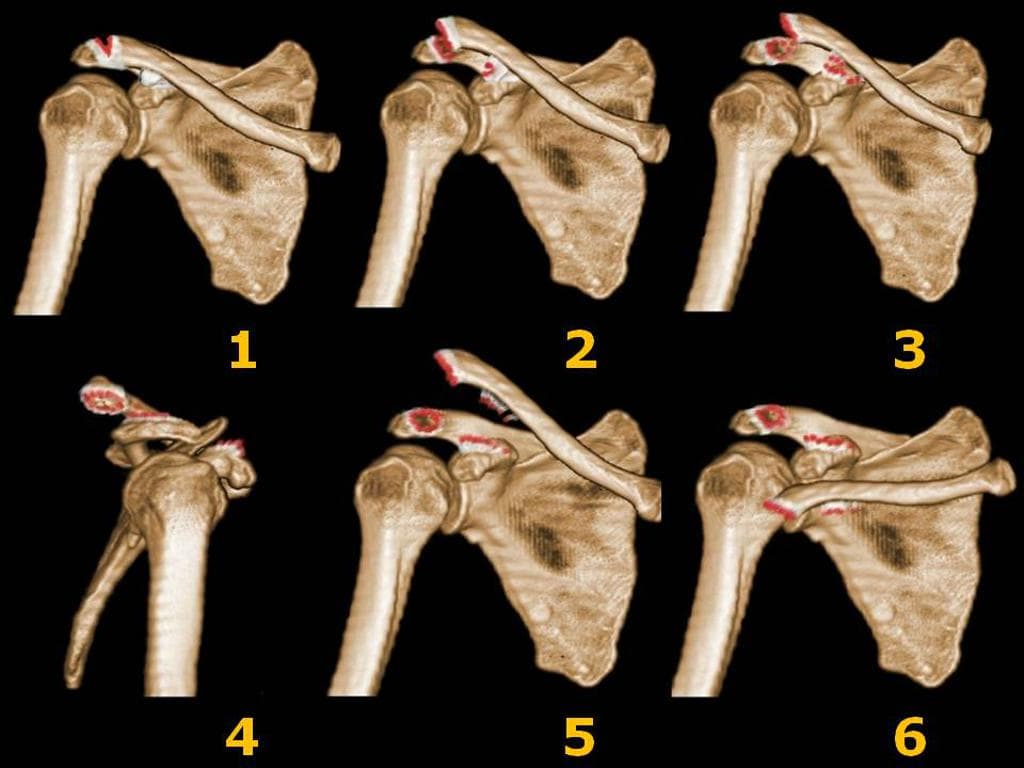

Rockwood Classification System of Acromioclavicular Joint Injuries (Hệ thống phân loại Rockwood các tổn thương khớp cùng đòn)

Rockwood Classification of Acromioclavicular Joint Injury (Phân loại Rockwood tổn thương khớp cùng vận động)